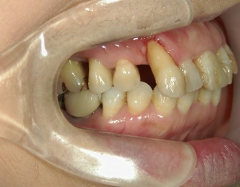

矯正歯科 治療前